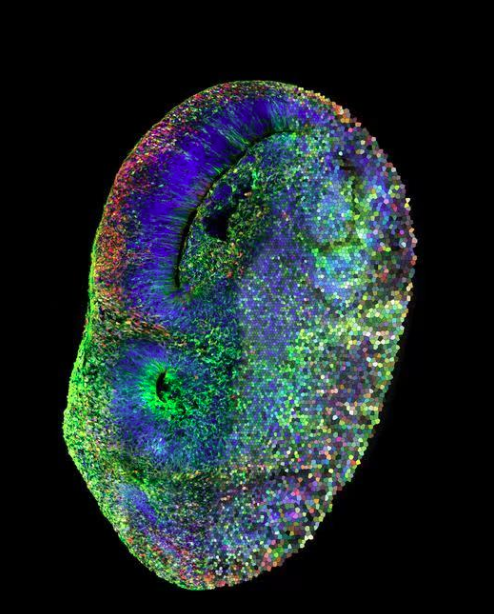

左半部分:人腦類器官圖像,攜帶紅色突變的細胞。右半部分:代表單個細胞的不同顏色的馬賽克圖,每個細胞都攜帶一個高置信自閉癥基因的突變

圖片來源:諾布里齊實驗室/IMBA